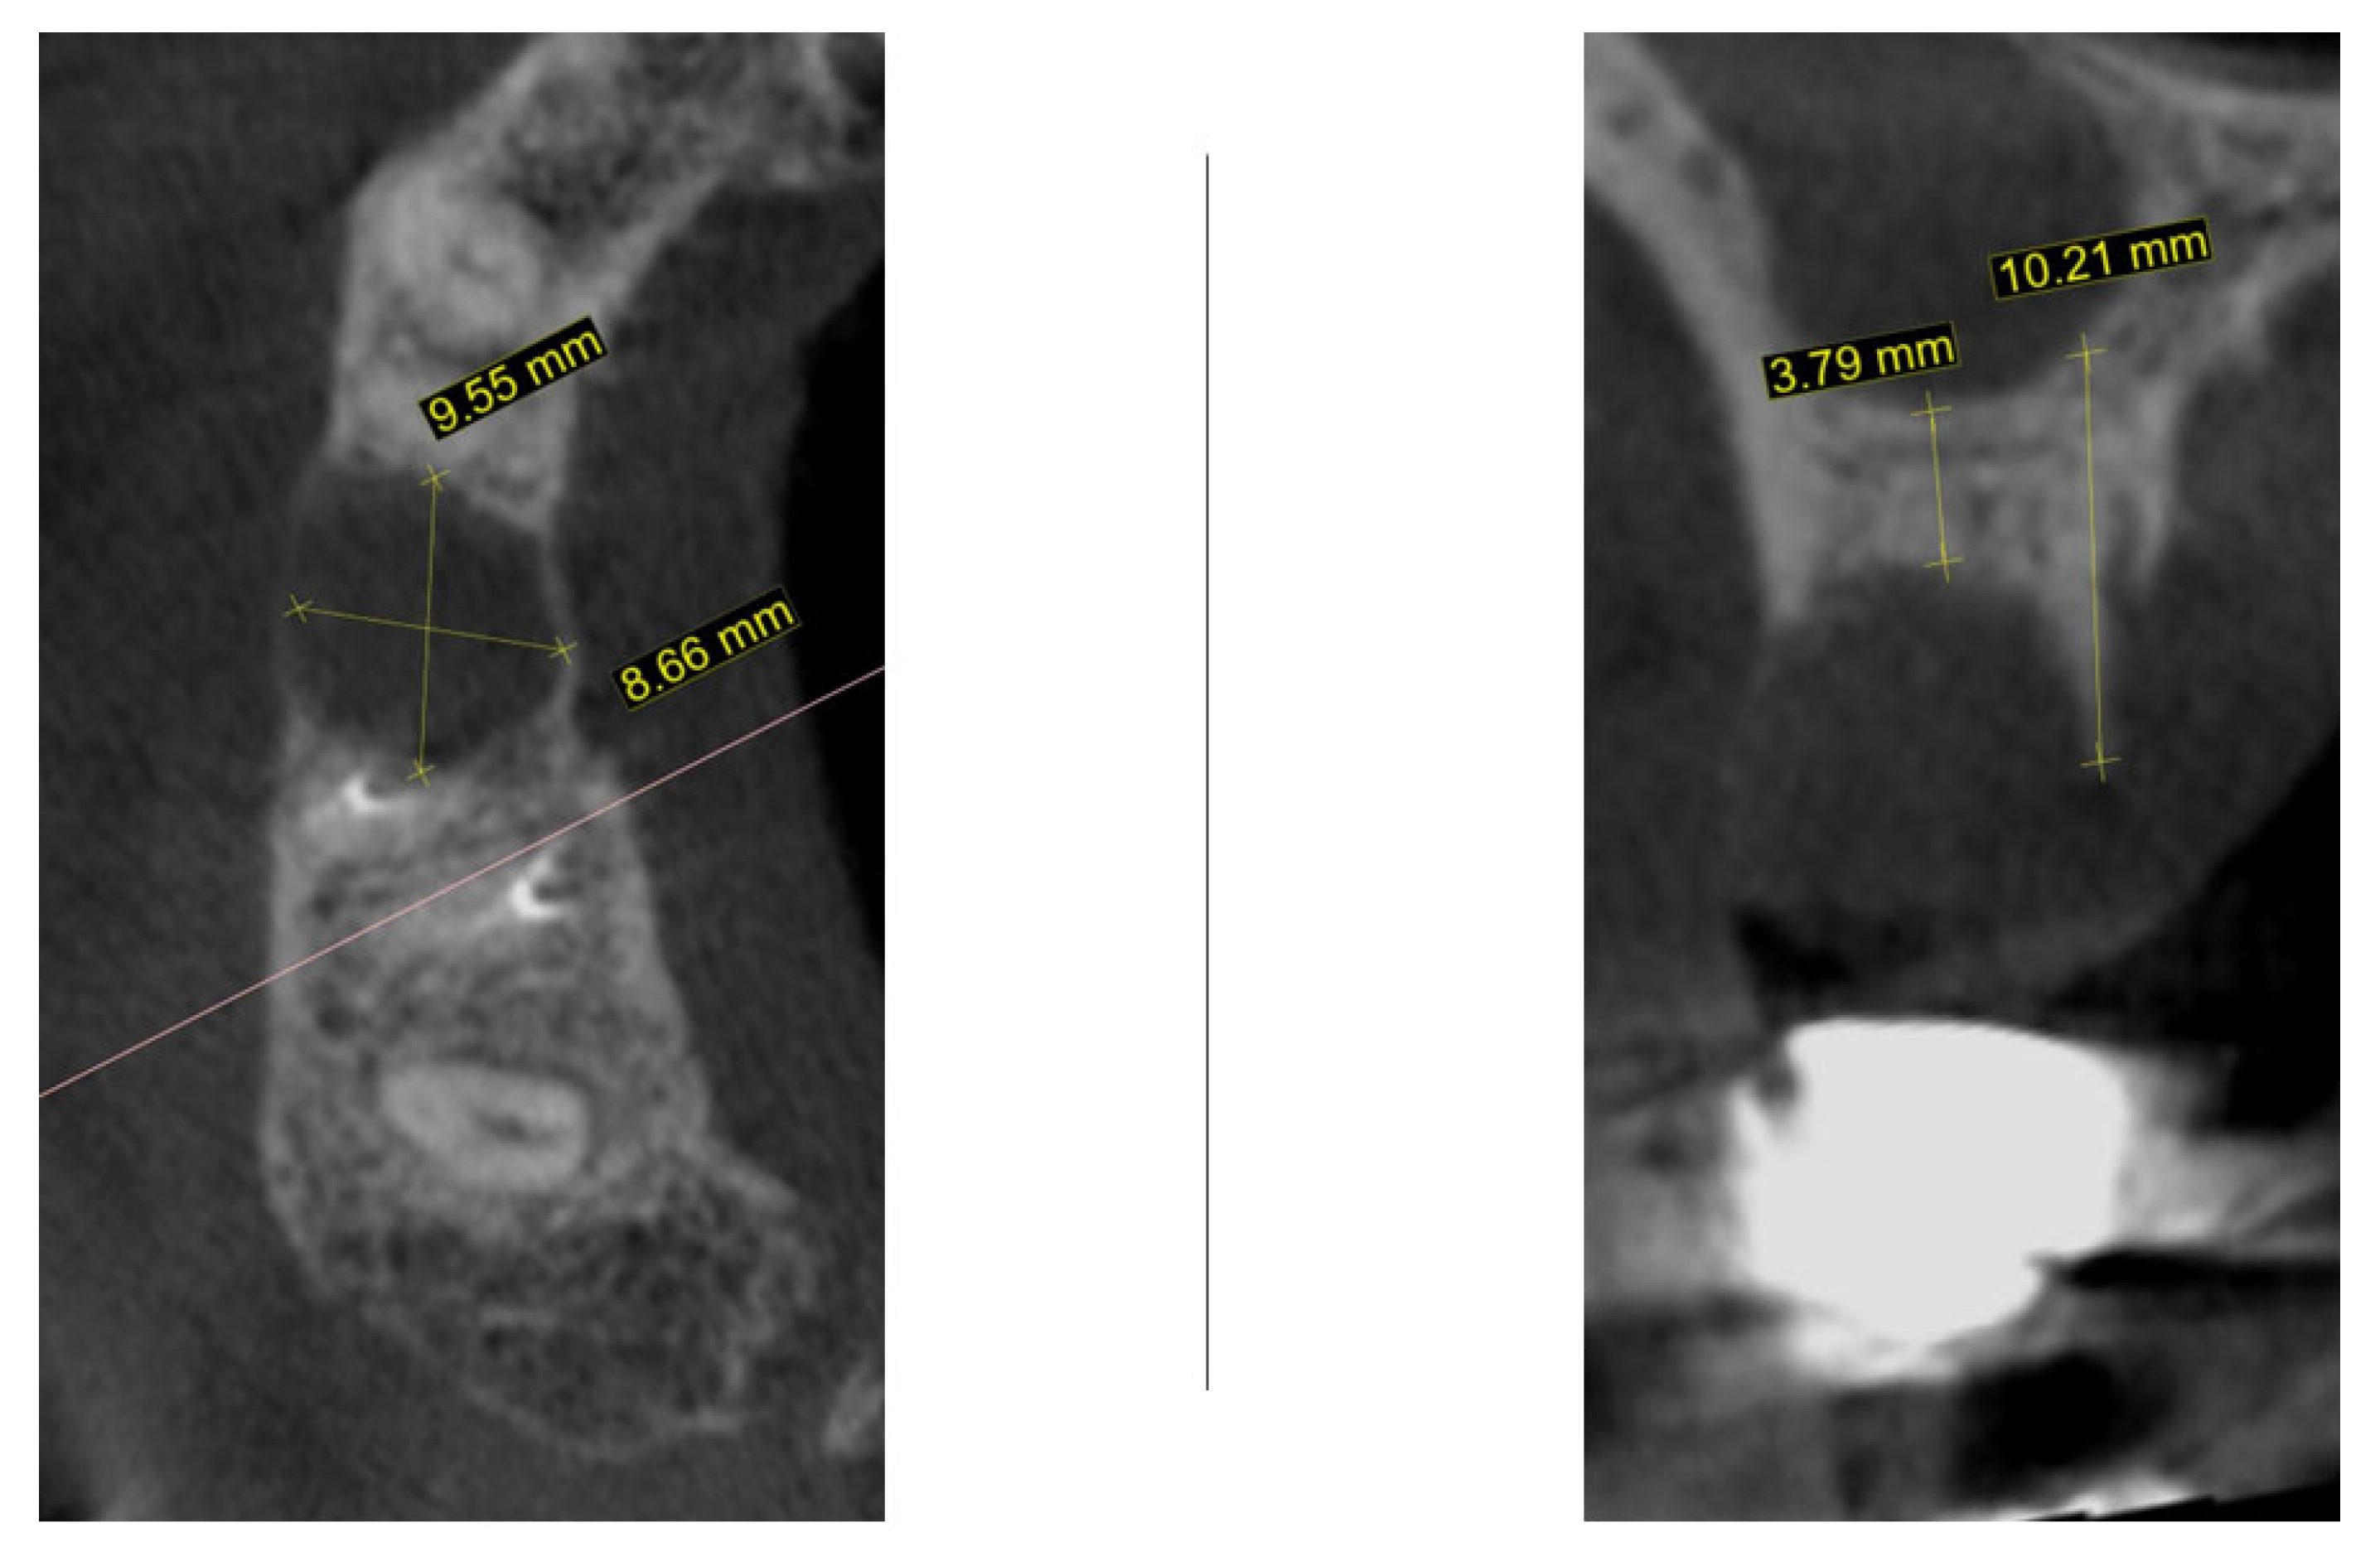

One month later, cone-beam computed tomography (CBCT) was performed to assess the morphology of the post-extraction site (Figure 2). For the region of interest (second right maxillary premolar), digital impressions were obtained using iTero Element Flex (Align Technology, Inc., Tempe, AZ, USA) and processed with Exoplan software, version 3.1 Rijeka (Exocad GmbH, Darmstadt, Germany). The iTero scanner applies a primarily surface-based registration complemented by anatomical landmarks, ensuring accurate fit and alignment. Using confocal imaging, it acquires detailed surface topography through point-and-stitch reconstruction, producing high-precision 3D models of teeth and soft tissues without the need for powder. Digital scans obtained during planning and at 3, 4, and 8 months post-surgery were superimposed using Exoplan (Exocad GmbH) software. Two-dimensional changes were assessed: (1) horizontal dimension—from the platform of the planned implant position to the corresponding buccal mucosal point, and (2) vertical dimension—from the implant platform to the buccal mucosal margin of the planned or placed restoration. The cross-sectional view demonstrated a large radiolucent zone with width of 9.5 mm and bucco-lingual dimension of 8.6 mm. In the sagittal plane, the residual vertical bone height measured 3.7 mm with a preserved palatal bony wall (10.2 mm). Although the assessment of these CBCT findings usually necessitates a bone augmentation procedure before implant placement, an alternative decision was taken to wait until the natural healing process is complete.

Figure 2.

CBCT one month following atraumatic extraction.

New cone-beam computed tomography (CBCT), performed to assess the morphology of the healed ridge, demonstrated a complete healed crestal bone with a bucco-lingual width of 8.2 mm. In the sagittal plane, the total vertical bone height measured 11.5 mm, suggesting adequate dimensions for implant placement without additional bone augmentation. The bone density measurement presented a high BMD value in the apical part of the crest while the density in the newly formed bone was relatively low (Figure 4).

Figure 4.

One year after autogenous healing of the extraction site.